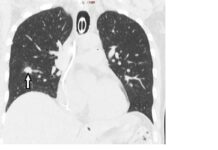

Pierwsza w Polsce termoablacja guza płuca

Radiolodzy interwencyjni szpitala Warszawskiego Uniwersytetu Medycznego przy ul. Banacha wykonali pierwszy w Polsce zabieg termoablacji guza płuca. U 50-letniego pacjenta – podczas jednego zabiegu...